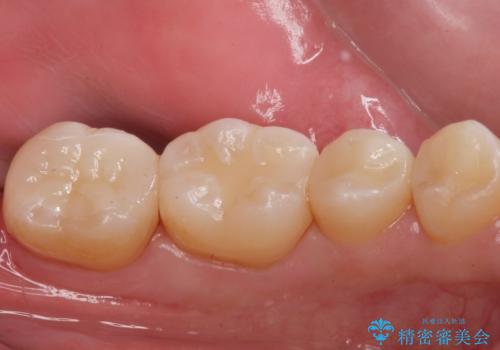

e-maxインレーによる治療

拡大鏡下でう蝕を全て除去してe-maxインレーにて治療を行いました。

e-maxインレーは二次的にう蝕になるリスクが

銀の詰め物や樹脂の詰め物に比べて低いです。